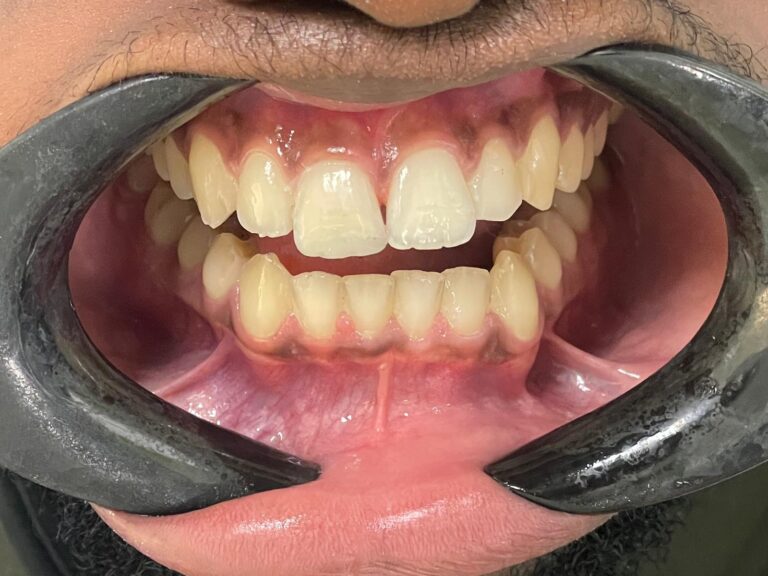

Case Study: Emergency Smile Restoration with Composite Bonding in Carshalton

At Carlton Dental, we understand how upsetting a dental emergency can be, particularly when it involves a visible front tooth. This case study outlines how we used composite bonding in Carshalton to help a young patient recover quickly after a traumatic injury. His smile and confidence were fully restored during a single visit to our clinic.

Our patient came to Carlton Dental following an accident during gymnastics, where he had fractured a front tooth. This was a repeat injury on the same tooth, which added to his concern about both appearance and the potential for permanent damage. Like many patients seeking emergency dental treatment, he arrived anxious and in need of immediate care.

The patient was seen by Dr Aliyah Janmohamed, one of our clinicians who specialises in cosmetic bonding and restorative dentistry. After a calm and reassuring assessment, we recommended composite bonding to rebuild the tooth on the same day.

In just one visit, the patient’s tooth was restored with excellent cosmetic results. The composite bonded tooth looked identical to his natural teeth, and his smile was back to normal. He left the practice smiling and visibly more confident. His parents also expressed their relief and appreciation for the speed and quality of care provided.